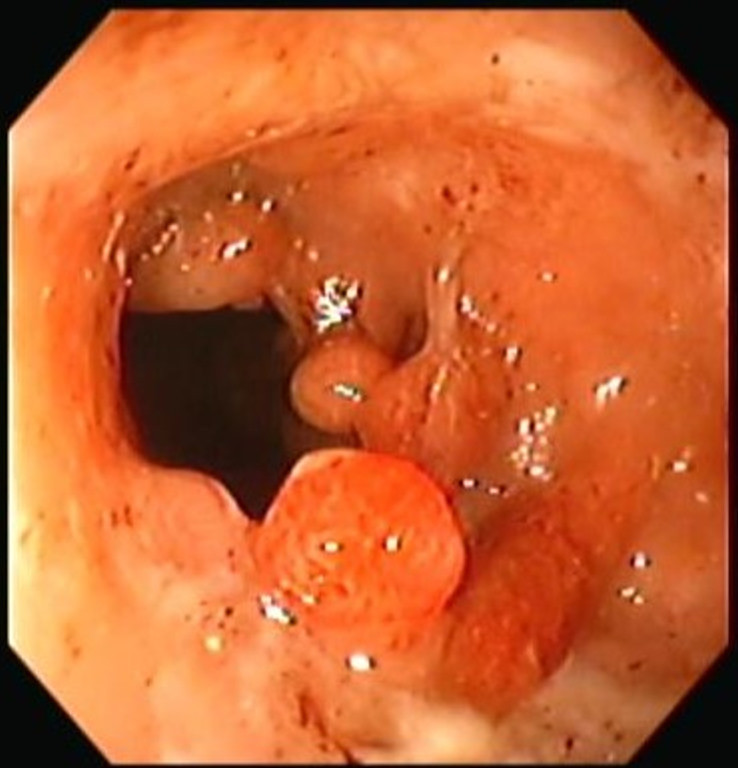

Pólipos de colon

Envíado por Dr. Carlos Ernesto Arévalo